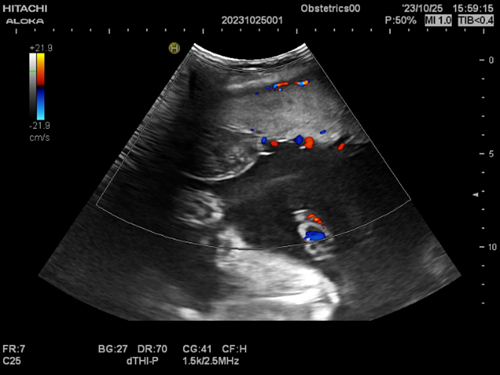

胎盘绒毛膜血管瘤

射频消融术后供血血流情况